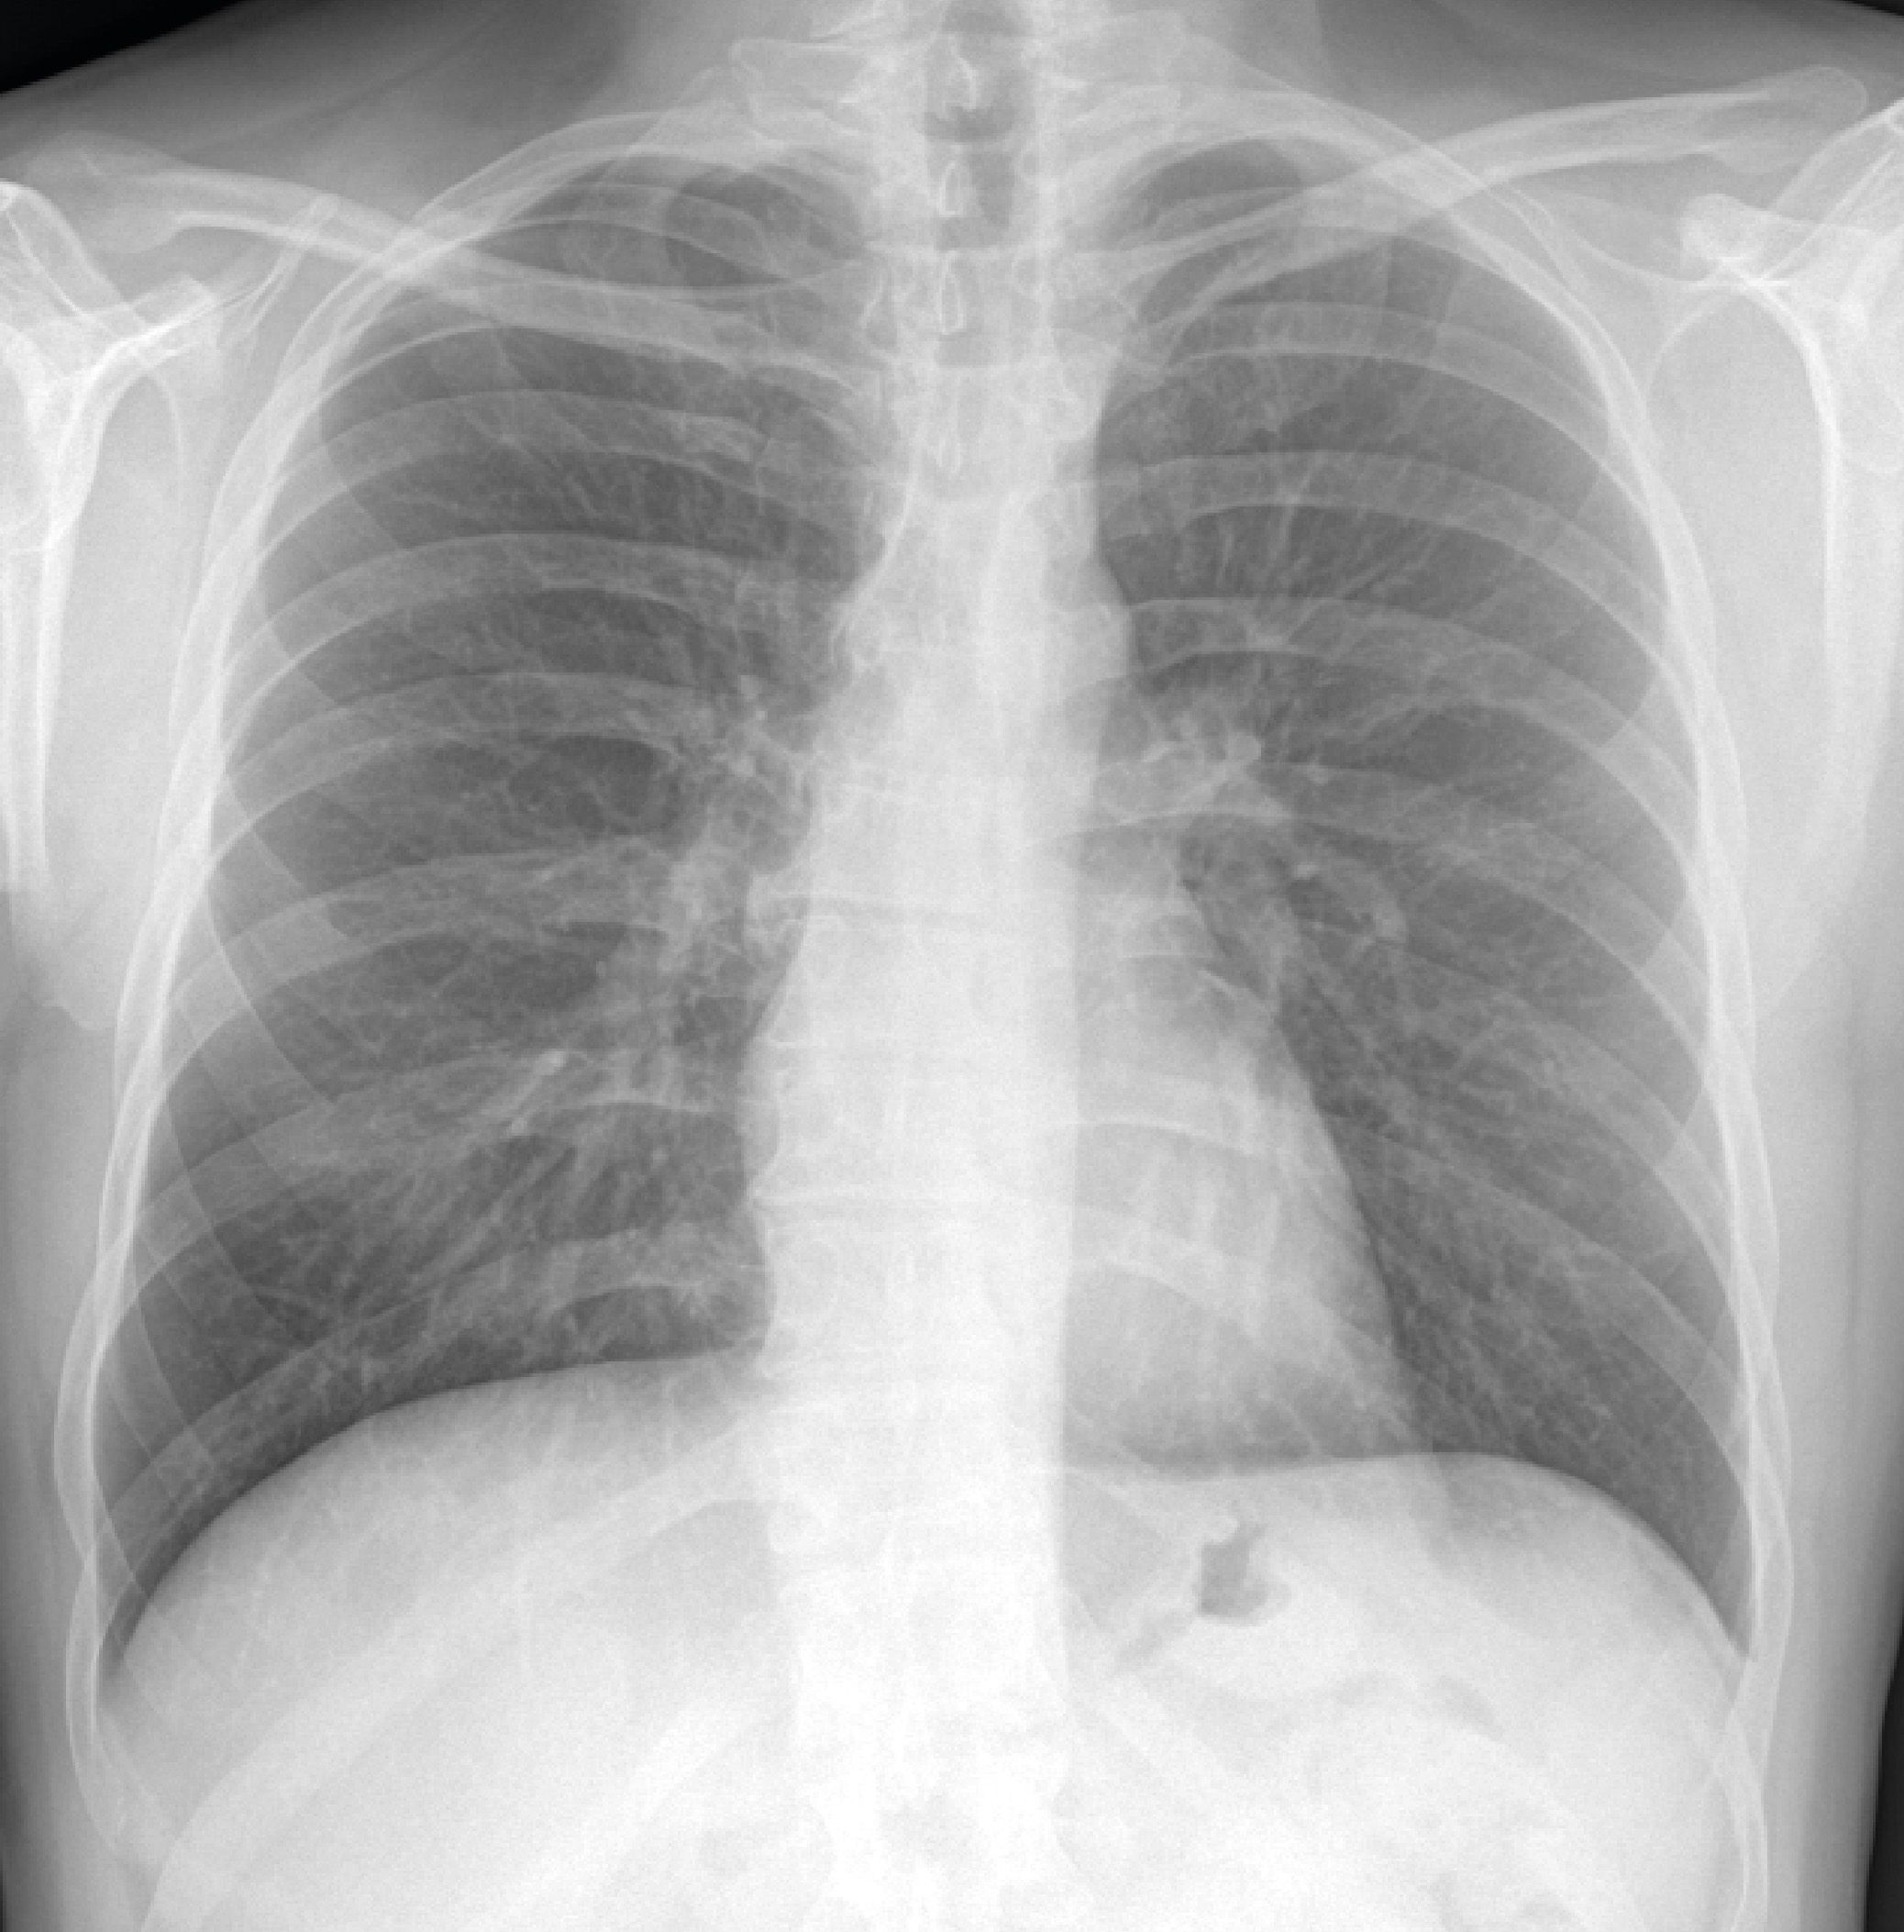

Bone Suppression è un algoritmo di post-processing che rimuove la componente ossea dall’immagine di una radiografia standard del torace favorendo la visibilità dei tessuti molli e di eventuali lesioni.

Interpretare una radiografia del torace può rivelarsi complicato: le strutture ossee a elevato contrasto presenti (coste e clavicole) possono oscurare del tutto o in parte le lesioni polmonari, ed essere perciò alla base di errori se non addirittura di mancate diagnosi.

Bone Suppression si propone di fornire un’immagine RX con migliore visibilità del campo polmonare mediante la riduzione del rumore causato dalle strutture ossee.

Grazie all'algoritmo di Bone Suppression è possibile, a partire da un'immagine radiografica standard del torace ottenuta con una singola esposizione e ricorrendo all'implementazione di un algoritmo basato sull'Al, rimuovere automaticamente le strutture ossee e ottenere un output di qualità elevata che faciliti la visibilità dei tessuti molli senza necessità di esporre il Paziente a dosi addizionali di radiazione.

Senza comportare appesantimenti o rallentamenti, senza richiedere ulteriori acquisizioni né comportare incrementi di dose di radiazione somministrata al Paziente, a partire dall’immagine RAW l’algoritmo di Bone Suppression genera un’immagine addizionale - anch’essa RAW - con la componente ossea rimossa. A quest’immagine aggiuntiva (e non sostitutiva della proiezione standard) potrà poi essere applicato il normale post-processing manuale eventualmente ritenuto necessario ai fini di visualizzazione e refertazione.